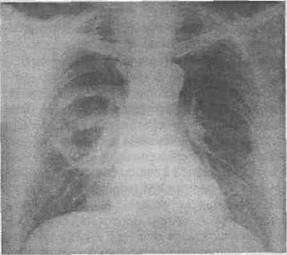

7. Examenul radiologic este eel mai important:

radiografia de fata si profil: imagine tipica de chist hidatic pulmonar (o opacitate ovalara, bine delimitata, omogena, intensitate subcostala prin inter-mediul careia se vad coastele). Imaginea clasica de opacitate rotunda trasa cu compasul nu este pa-tognomonica pentru chist hidatic pulmonar (fig. 2).

Fig. 2 - Radiografie profil imagine tipica de chist hidatic lob infe- ^ p